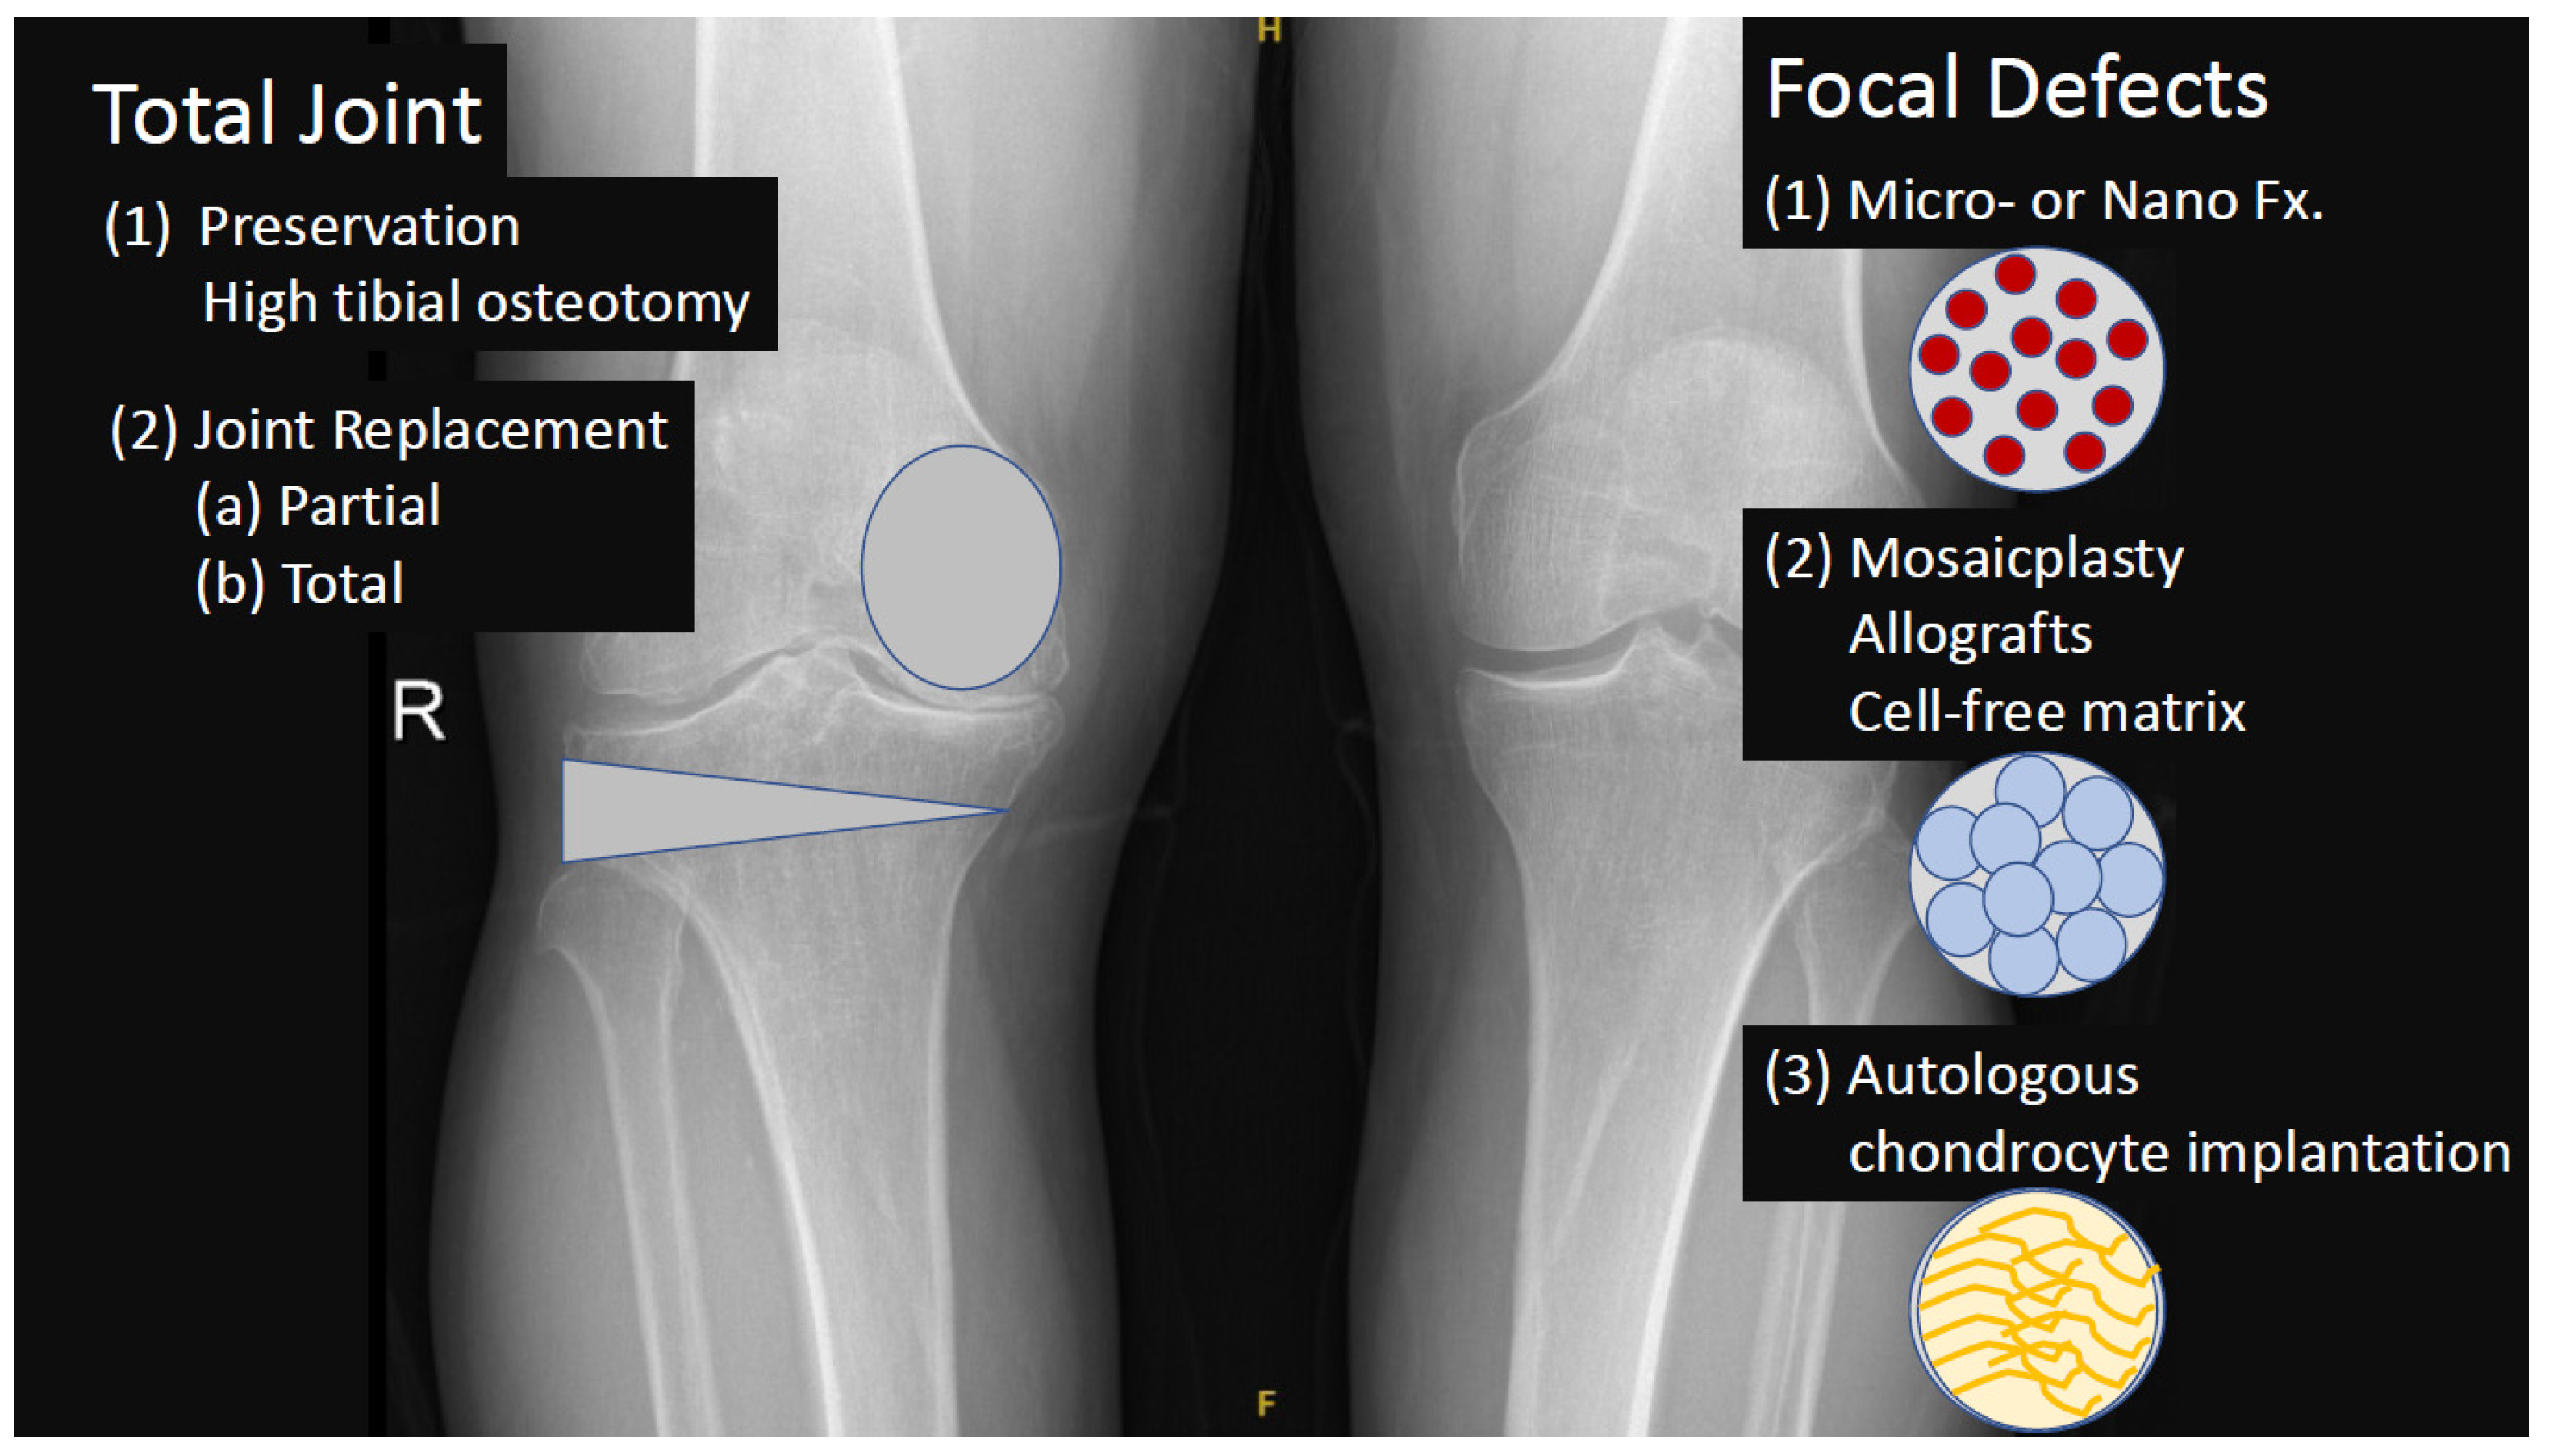

3. Definition and Treatment of Osteoarthritis (OA)